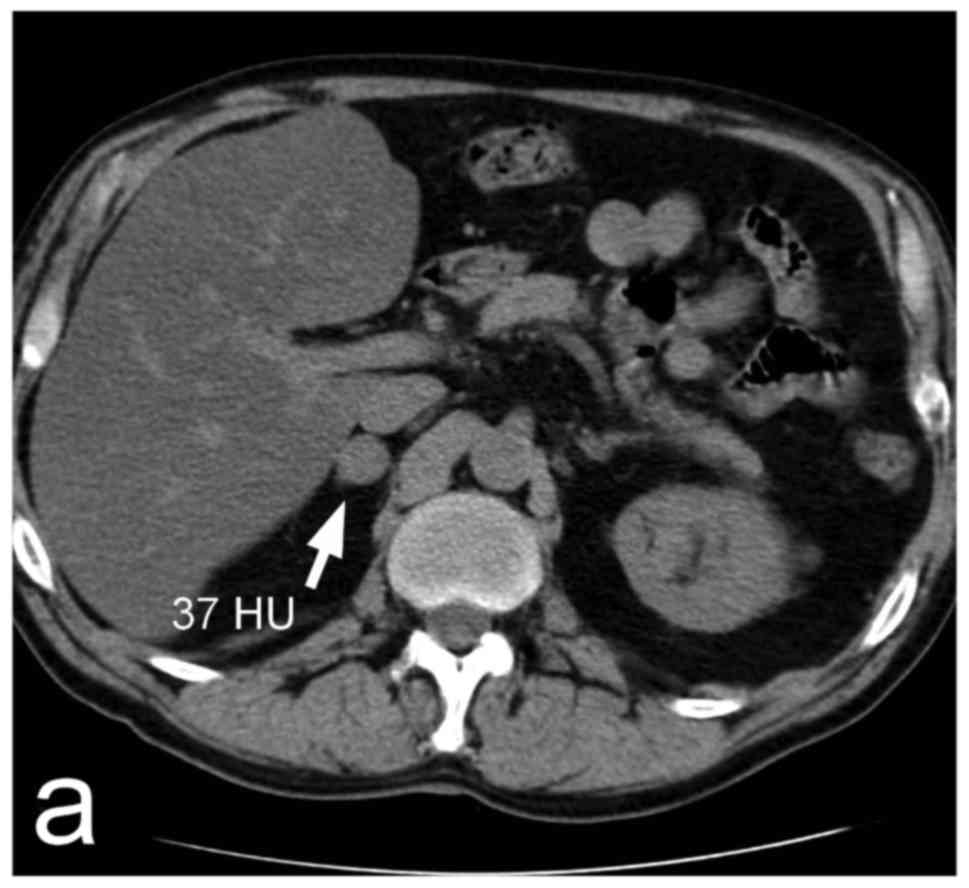

Pheochromocytoma In An Incidentally Discovered Asymptomatic Cystic Adrenal Mass Mayo Clinic Proceedings